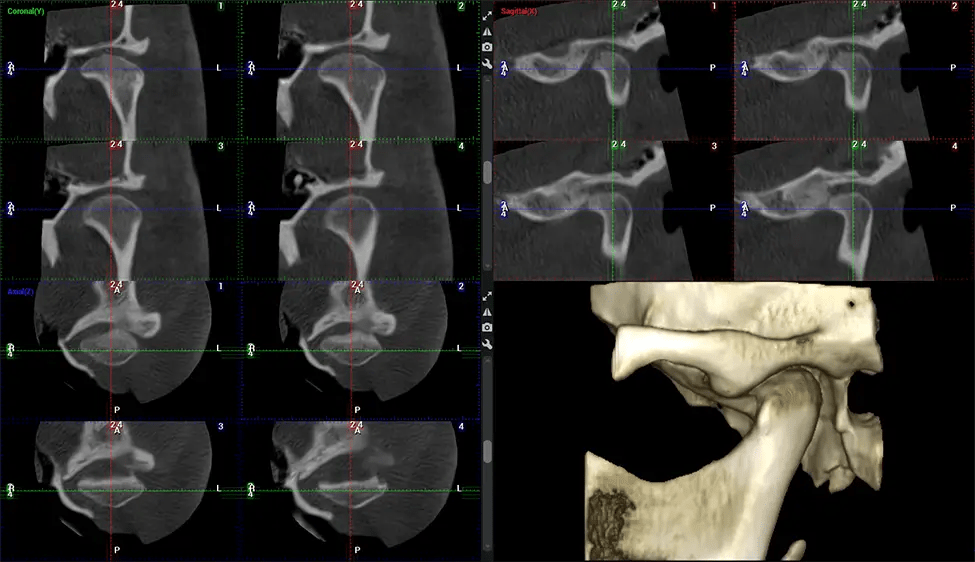

Planmeca Viso G7 CBCT (Cone Beam CT Scan) está diseñado para superar las demandas de los líderes de la industria, los especialistas y las grandes instituciones. Tiene un gran sensor de ø25×30 cm con cuatro cámaras integradas. Puede capturar tamaños de volumen ilimitados, desde ø3×3 cm hasta ø30x30cm, capturando el casquete escutelario a través de C7 en la columna cervical. Planmeca Viso G7 ofrece el escaneo de volumen único más grande de la industria de ø30×19 cm. Está preparado para manejar modalidades de imágenes avanzadas como la tecnología Planmeca ProFace® y Planmeca 4D™ Jaw Motion. El soporte occipital para la cabeza permite una visión sin obstáculos del tejido facial.

Planmeca es el único fabricante clínicamente probado que reduce drásticamente la radiación del paciente sin sacrificar la calidad de la imagen. Planmeca Ultra Low Dose™ logra una reducción promedio de la dosis del 77% sin una reducción estadística en la calidad de la imagen, lo que permite a los médicos incorporar imágenes 3D en protocolos de rutina con una radiación efectiva al paciente a menudo inferior a la de las imágenes intraorales 2D.. Esto aumenta la atención al paciente, permite a los médicos diagnosticar más odontología y, a menudo, antes en la progresión de la enfermedad, que con imágenes 2D solas.

Las unidades Planmeca 3D también incluyen la única tecnología de corrección y detección de movimiento del paciente de la industria, Planmeca CALM™. Esta tecnología corrige el movimiento durante la adquisición de CBCT reduciendo el riesgo de repeticiones.